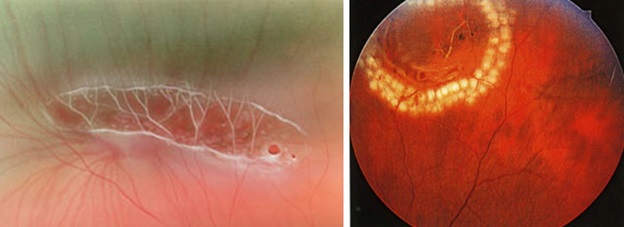

Prevention (but not immunity) for retinal detachment exists — it is laser coagulation of areas on the retina, which may be the cause. These are certain types of dystrophies, tractions, breaks — but, unfortunately, not every patient believes in the need for these procedures, especially if nothing is bothering you.

存在视网膜脱离的预防措施(但不是免疫措施)-视网膜区域的激光凝结可能是原因。 这些是某些类型的营养不良,牵引,休息-但是,不幸的是,并非每个患者都认为需要这些程序,尤其是在没有任何事情困扰您的情况下。

Types of dystrophies, dangerous in terms of delamination, have already been mentioned in posts earlier:

较早前的帖子中已经提到了营养不良的类型,它们在分层方面很危险:

How to “sew up” the retina and should it be done? 如何“缝合”视网膜,应该怎么做?The names of dystrophies are non-standard: “Lattice dystrophy”, “dystrophy by the type of snail track”, “traction”, “frivolous”, “white without impression”, “perforated breaks with and without lid”, “valve breaks” and others.

营养不良的名称是非标准的:“晶状体营养不良”,“按蜗牛轨道类型的营养不良”,“牵引力”,“轻浮”,“白色无印痕”,“有盖和无盖的穿Kong破裂”,“瓣膜破裂” “ 和别的。

Unfortunately, retinal glue has not yet been invented, but the laser turned out to be very effective. The laser “welds” the retina to the underlying tissues along the edges of all the breaks. After the application of laser coagulates, local inflammation occurs, and then a microtubule is gradually formed (5-7 days) on the choroid. Therefore, it makes sense to leave “heavy water” in the eye for a week. In some cases, this is enough to keep the retina in place, but it may be necessary to continue to hold the retina to form more durable adhesions. In such cases, silicone oil is used, which fill the eye cavity.

不幸的是,视网膜胶尚未被发明,但是激光被证明是非常有效的。 激光沿着所有断裂的边缘将视网膜“焊接”到下面的组织。 施加激光凝结后,发生局部炎症,然后在脉络膜上逐渐形成微管(5-7天)。 因此,将“重水”放在眼中一周是有意义的。 在某些情况下,这足以将视网膜保持在适当的位置,但是可能有必要继续保持视网膜以形成更持久的粘连。 在这种情况下,将使用硅油填充眼Kong。